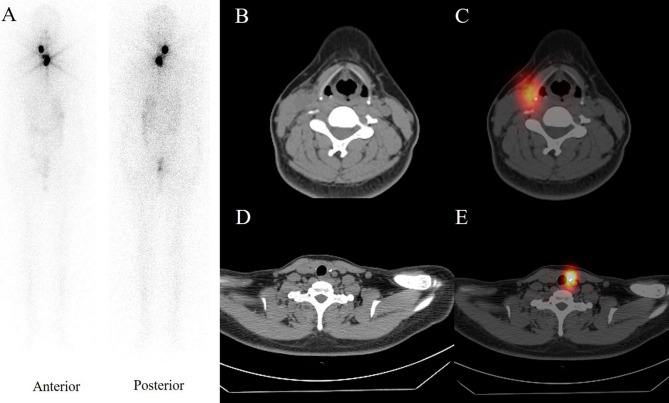

Case presentation: A 33-year-old Chinese woman presented to the hospital with an incidental mass in her right neck. Ultrasonography and magnetic resonance imaging revealed a giant right cystic mass in the inferior submandibular gland. The patient underwent mass dissection. Histopathological assessment indicated metastatic papillary carcinoma from the thyroid. Total thyroidectomy and bilateral selective neck dissection were performed. Meticulous pathological examination revealed no lesions in the thyroid. After 18 months of follow-up, no signs of recurrence were noted.